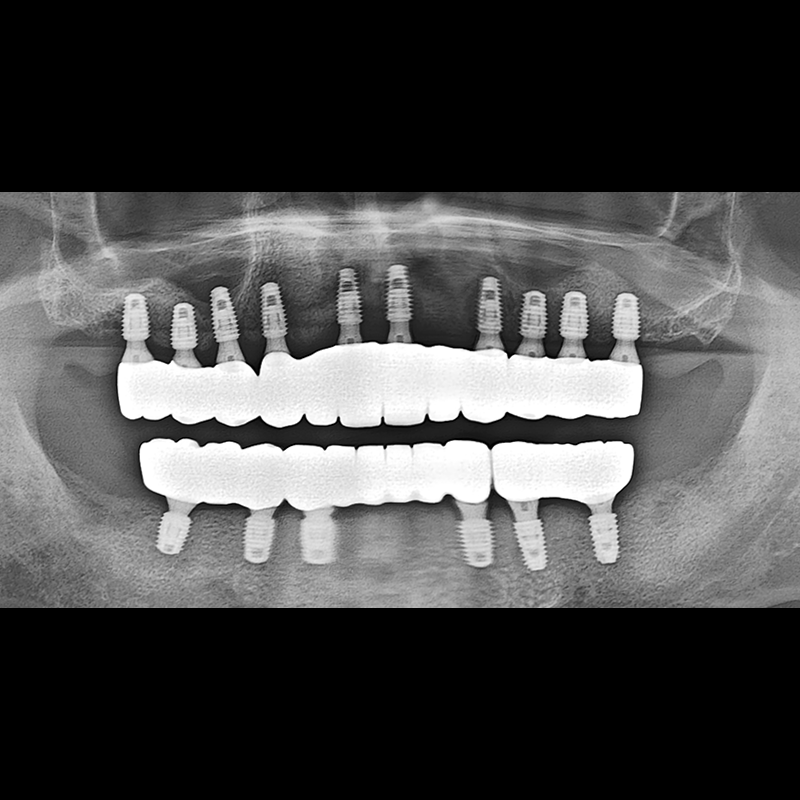

BEFORE AFTER

种植牙前后的照片 2025.05.30

在缺失的牙齿部分和难以挽救的牙齿位置植入了种植牙。